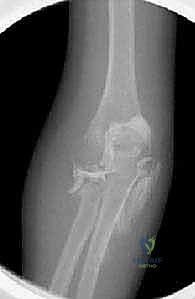

2. التصوير الشعاعي (X-Rays)

هو الخطوة الأساسية لتأكيد الكسر. يتم التقاط صور من زوايا متعددة (أمامية خلفية، وجانبية، ومائلة).

* علامة وسادة الدهون (Fat Pad Sign / Sail Sign): في بعض الأحيان، خاصة في كسور النوع الأول غير المزاحة، قد لا يظهر خط الكسر بوضوح في الأشعة. في هذه الحالة، يبحث الدكتور هطيف عن "علامة الشراع" أو ارتفاع وسادة الدهون المحيطة بالمرفق في الصورة الجانبية، والتي تدل على وجود نزيف مفصلي (Hemarthrosis) يؤكد وجود كسر خفي.